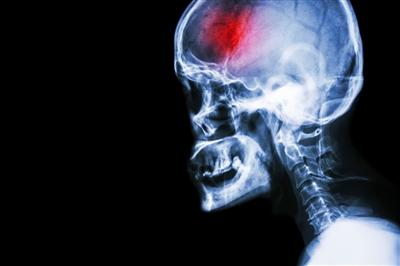

CONCUSSION WHAT YOU NEED. The symptoms can present immediately and be short-lived or the onset of symptoms may be delayed and start to occur sometime after the initial injury.

Concussion symptoms can last anywhere from a few days to a few months depending on the severity of the injury. In this prospective study of pediatric SRC patients who were evaluated at a multi-disciplinary concussion program a median of 5 days post-injury 167 reported experiencing. Learn more for more Ideas and suggestions.

Symptoms and signs of concussion in baby When you think of general concussion symptoms issues like headache confusion nausea and dizziness may come to mind. Interruption in the babys sleeping habits either sleeping more or less. Ad Check out 12 it may change your Life.

In young babies signs of a concussion can include. Symptoms in Babies and Toddlers. Repeated vomiting Loss of consciousness longer than 30 seconds Changes in behavior such.

For some people the symptoms after a concussion may not become apparent until later in the day says Beth Kolar advanced clinician at Bryn Mawr Rehabilitation Hospital. Trouble concentrating Memory problems Irritability and other personality changes Sensitivity to light and noise Sleep disturbances Depression and. May 12 2014 1034 AM HealthDay.